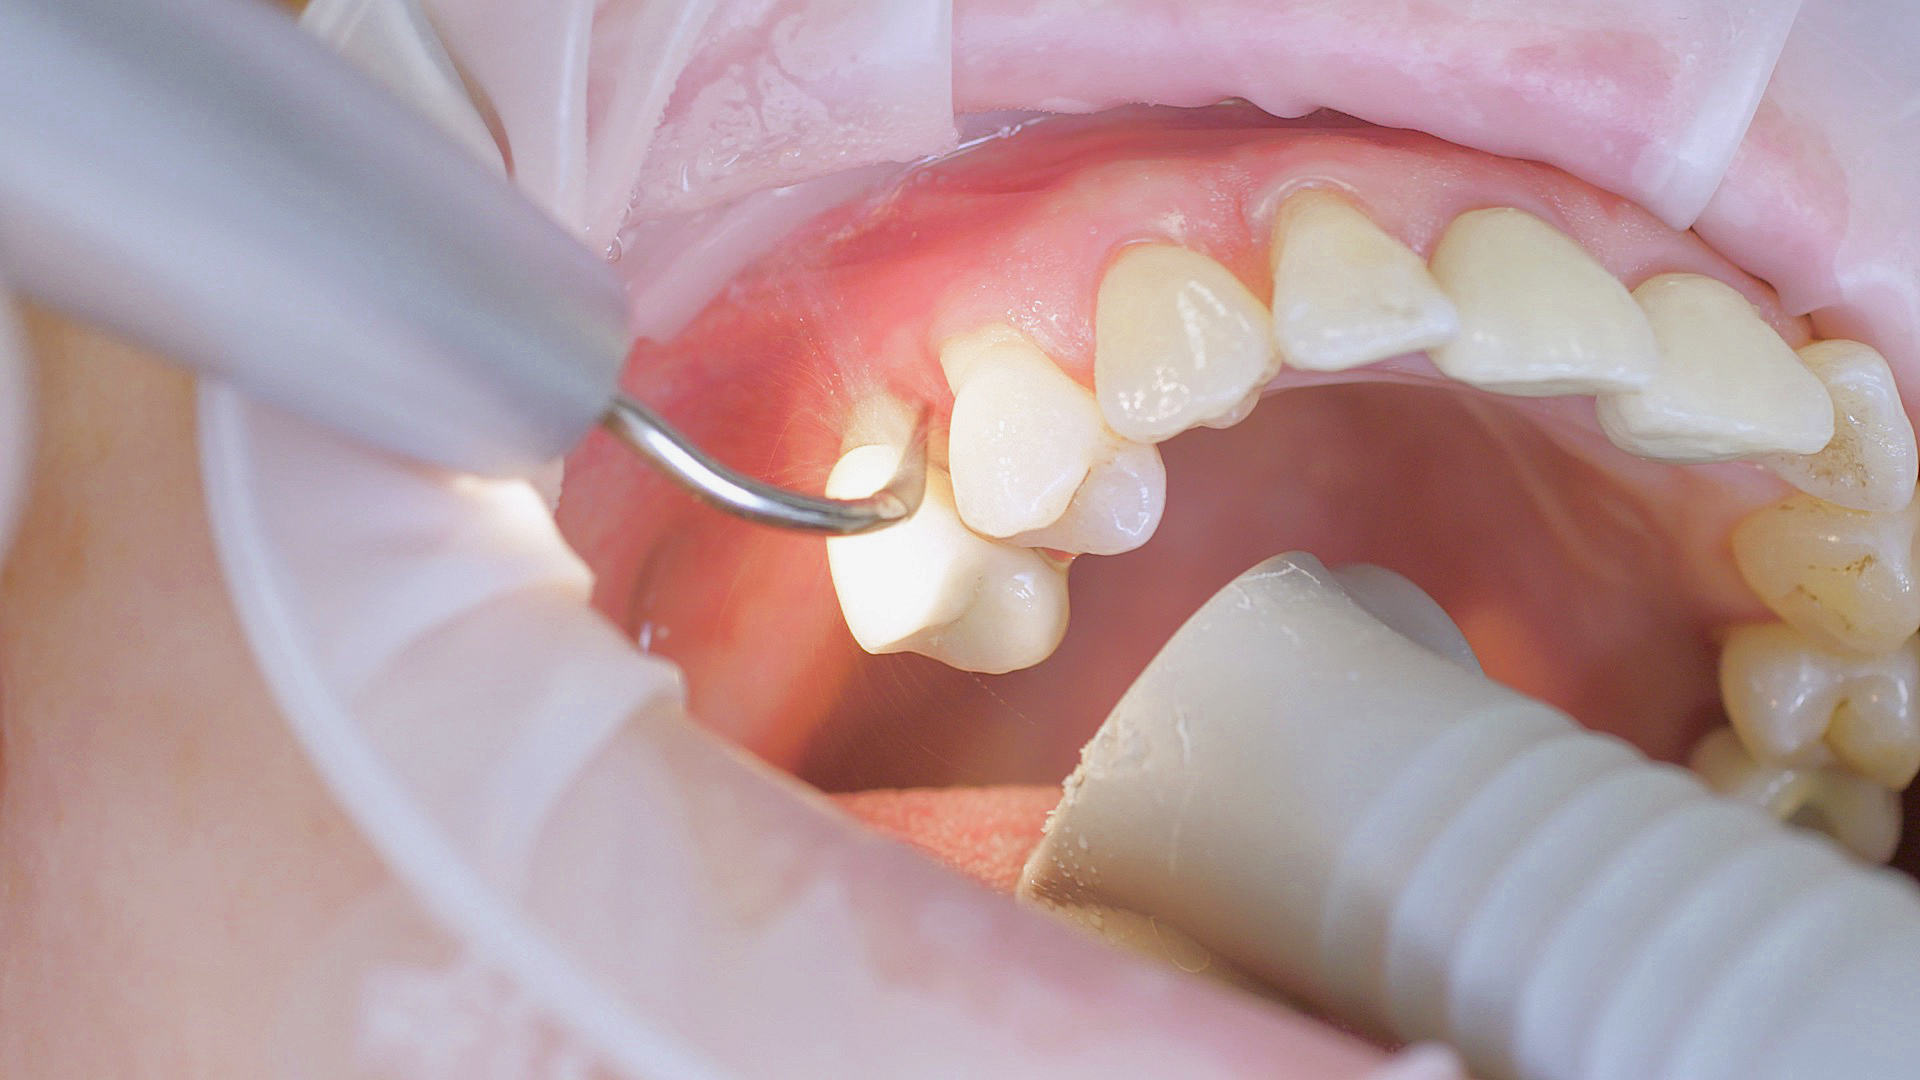

Implants and superstructures can be successfully cleaned with ultrasonic devices and special plastic instruments

Fig. 3: Implants and superstructures can be successfully cleaned with ultrasonic devices and special plastic instruments during postoperative care or non-surgical therapy.

Healthy peri-implant tissue does not show any signs of redness, swelling or bleeding, neither does it secrete pus when probed.[5] Based on the consensus document, Prof. Giovanni Salvi explained the importance of regu- lar probing — preferably with a flexible probe, as implant components often tend to obstruct the procedure.[5] In the case of mucositis or initial peri-implantitis already being present, the non-surgical removal of hard deposits and biofilm should be attempted first. For this purpose, ultra- sonic power and special instruments designed to protect the implant should be employed (Fig. 3; piezo scaler Tigon+ with 1I, W&H). In case of no remission, the recall frequency needs to be increased. However, specific recommendations, applicable to individual cases, are not yet available in this context.[15]